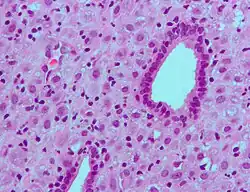

Micrograph of decidualized endometrium due to exogenous progesterone. H&E stain.

Micrograph of decidualized endometrium due to exogenous progesterone. H&E stain. -

Micrograph of decidualized endometrium due to exogenous progesterone. H&E stain.

Micrograph of decidualized endometrium due to exogenous progesterone. H&E stain. -